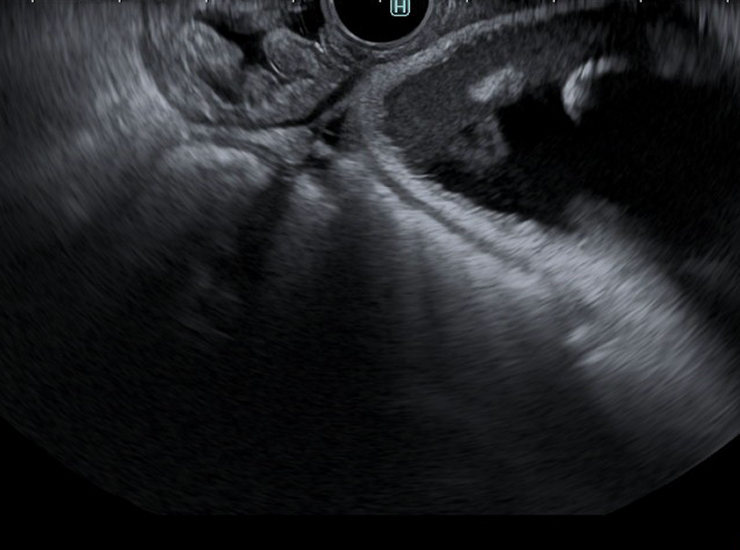

Contrast Harmonic Imaging (CHI)

CHI is the application of an ultrasound contrast agent to traditional ultrasonography to characterize focal liver lesions. Contrast agents are comprised of gas-filled microbubbles that are administered intravenously. The difference in echogenicity between the gas in the microbubbles and the soft tissue surrounding the body is immense, which improves the visualization and assessment of tissue vascularity.2